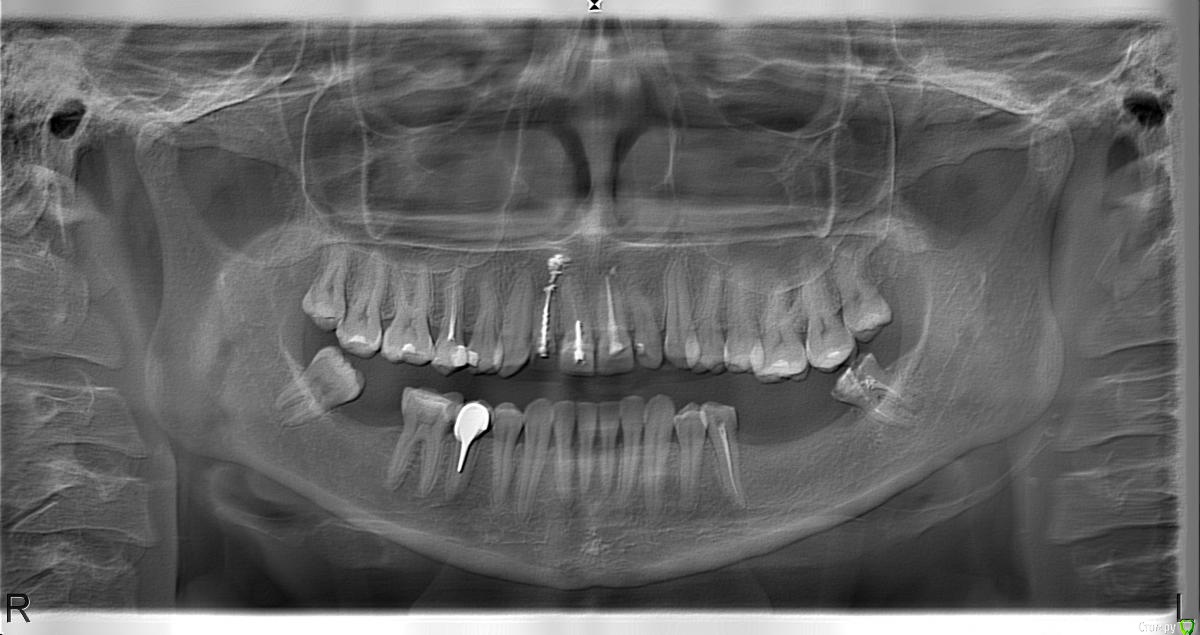

ALEXEY_325 Опубликовано 25 февраля, 2015 Поделиться Опубликовано 25 февраля, 2015 Здравствуйте! Моей жене 35 лет. требуется имплантация 36 и 37, видимо удаление 38, лечение 35. Необходима ли костная пластика?Как вы считаете, на 36 и 37 поставить два импланта или безопаснее 3? и Соответственно 2 или 3 коронки? Необходимо ли что то делать с верхними выдвинувшимися 26 и 27?Извиняюсь за повтор, очень ждем ваших мнений! https://cloud.mail.ru/public/c72abb0b47f1/2015.rar https://cloud.mail.ru/public/64a73e50d052/RX01.bmp Ссылка на комментарий

Aquarius Опубликовано 25 февраля, 2015 Поделиться Опубликовано 25 февраля, 2015 Надо посмотреть что с шириной кости в области 36-37. Выдвинутые зубы покрыть накладками/коронками.Или задвинуть обратно. 38 - удалить Ссылка на комментарий

Aquarius Опубликовано 25 февраля, 2015 Поделиться Опубликовано 25 февраля, 2015 Посмотрел. Если все правильно выставил, то до н/ч канала 10,5 мм. Ширины чуть-чуть надо добавить. Вобщем пластику желательно Ссылка на комментарий

ALEXEY_325 Опубликовано 26 февраля, 2015 Автор Поделиться Опубликовано 26 февраля, 2015 Посмотрел. Если все правильно выставил, то до н/ч канала 10,5 мм. Ширины чуть-чуть надо добавить. Вобщем пластику желательноНасколько опасна костная пластика? Нам это представляется очень серьезной операцией?А имплантов достаточно два или будет опасная нагрузка на них? Ссылка на комментарий

Aquarius Опубликовано 26 февраля, 2015 Поделиться Опубликовано 26 февраля, 2015 Насколько опасна костная пластика? Нам это представляется очень серьезной операцией?А имплантов достаточно два или будет опасная нагрузка на них? Не переживайте, операция не сложная. Можно даже сказать рядовая, только надо опытного хирурга. Имплантов ставьте 2. Если ортопед сделает цельным мостом, то можно ставить два импланта по 8 мм. длины. Такой вариант тоже имеет право на жизнь. Ссылка на комментарий